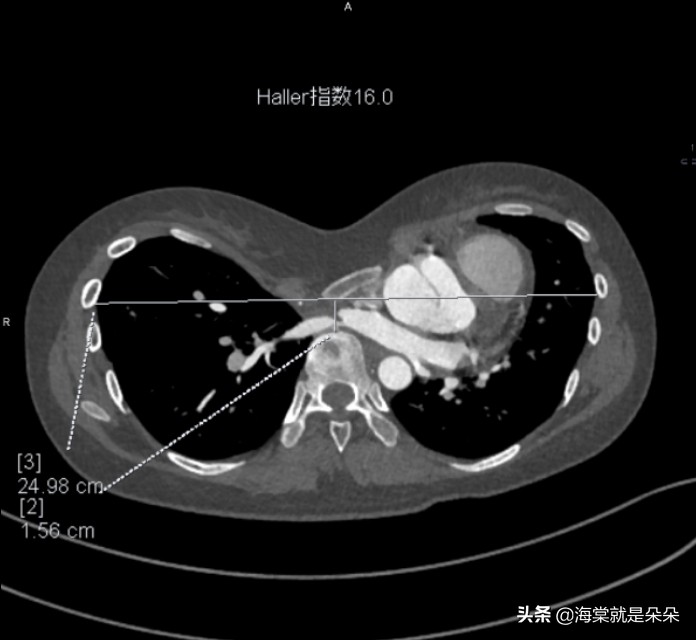

国际上评估漏斗胸的畸形指数,普遍使

用 Haller指数,关于漏斗最深点到脊柱前方距离、胸骨最凹陷处层面胸廓的最大横径。

正常人的 HI 平均指数是 2.52,漏斗胸患者则超过 3.2,大于 3.5 为重度漏斗胸,3.25 到 3.5 为中度,小于 3.25 为轻度。

这个女孩20岁才来就诊,Haller指数达到了16!胸骨体都快贴到胸椎了!心脏大血管受压迫移到左边,主动脉窦膨大!